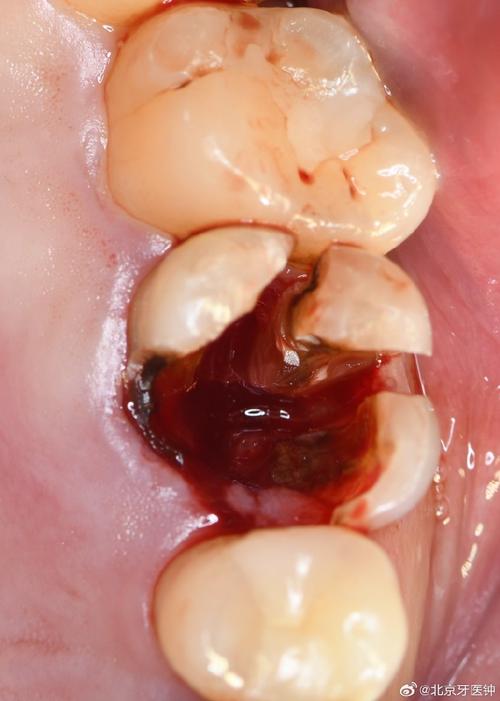

种牙植骨手术需在牙槽骨内制备种植窝、植入骨粉,这一过程可能损伤周围小血管,导致术后短期内少量渗血,属于正常现象,但若出血量较大或持续时间较长,可能与以下因素有关:

- 手术创伤:术中操作可能损伤牙龈黏膜、骨膜或小动脉,尤其骨粉植入后局部血供丰富,若缝合不严密或压迫不足,易引发出血。

术后少量渗血(唾液中带血丝、24小时内出血量<5ml)通常无需特殊处理,可通过局部压迫、调整护理习惯缓解;若出血量较大(如血凝块持续脱落、出血超过30ml/小时)或伴随头晕、心慌等不适,需立即采取措施: